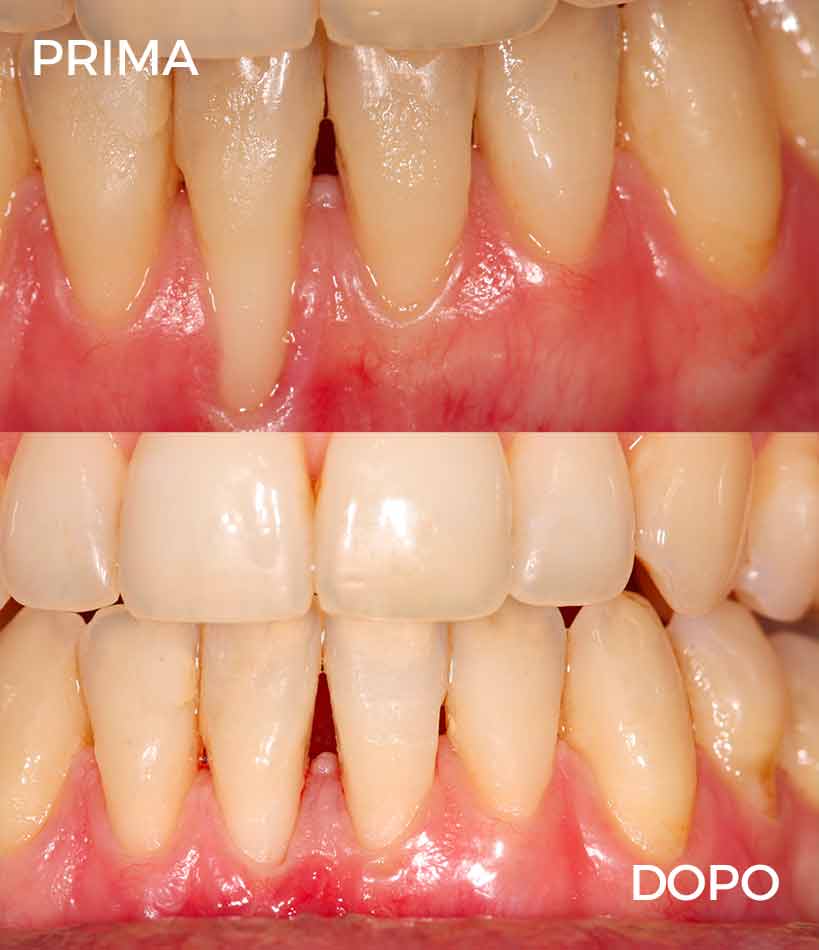

Prima & Dopo

Paziente con recessioni gengivali

Paziente con recessioni gengivali, una condizione che può causare sensibilità dentale, disagio estetico e, nel tempo, aumentare il rischio di problemi parodontali.

Grazie a un intervento di chirurgia mucogengivale, è stato possibile coprire le recessioni, ripristinando una corretta salute dei tessuti gengivali e migliorando in modo significativo sia la funzionalità che l’estetica del sorriso.

Un trattamento mirato e minimamente invasivo che permette di proteggere i denti, ridurre la sensibilità e restituire armonia al sorriso.

Paziente con recessioni gengivali multiple

Paziente con recessioni gengivali multiple, una condizione che interessa più elementi dentari e che può compromettere sia l’estetica del sorriso sia il benessere gengivale.

Attraverso un unico intervento di chirurgia mucogengivale correttiva, è stato possibile trattare in modo mirato tutte le recessioni, migliorando la protezione dei denti e ristabilendo l’equilibrio dei tessuti gengivali.

Un approccio efficace che consente di ottenere risultati armonici, funzionali e duraturi, con un netto miglioramento del comfort e dell’estetica complessiva del sorriso.

Correzione delle Recessioni Gengivali

Il paziente presentava recessioni gengivali con esposizione della superficie radicolare, associate a sensibilità dentale e a un’alterazione dell’estetica del sorriso.

Una condizione che, oltre all’aspetto estetico, può aumentare il rischio di carie radicolari e compromettere la salute parodontale nel tempo.

Soluzione adottata:

Intervento di chirurgia muco-gengivale finalizzato alla copertura delle recessioni e al ripristino di un corretto profilo gengivale.

La tecnica utilizzata consente di proteggere le radici esposte, migliorare la stabilità dei tessuti e ottenere un risultato armonico e naturale.